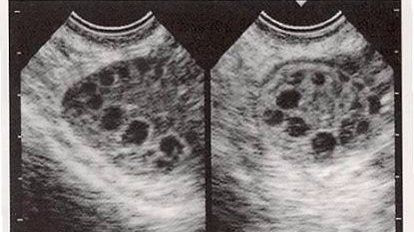

多囊卵巢可以怀孕吗

不少的不孕症都是多囊卵巢造成的。有时即使可以怀孕,但也很容易流产,因为多囊卵巢综合征造成内分泌失调,无法提供胚胎早期发育时所需要一些营养,自身的激素补充不上,所以会造成胚胎的停止发育和流产。建议到正规的不孕不育专科医院做相关方面的检查,查明具体病因,科学针对性的进行调理治疗。